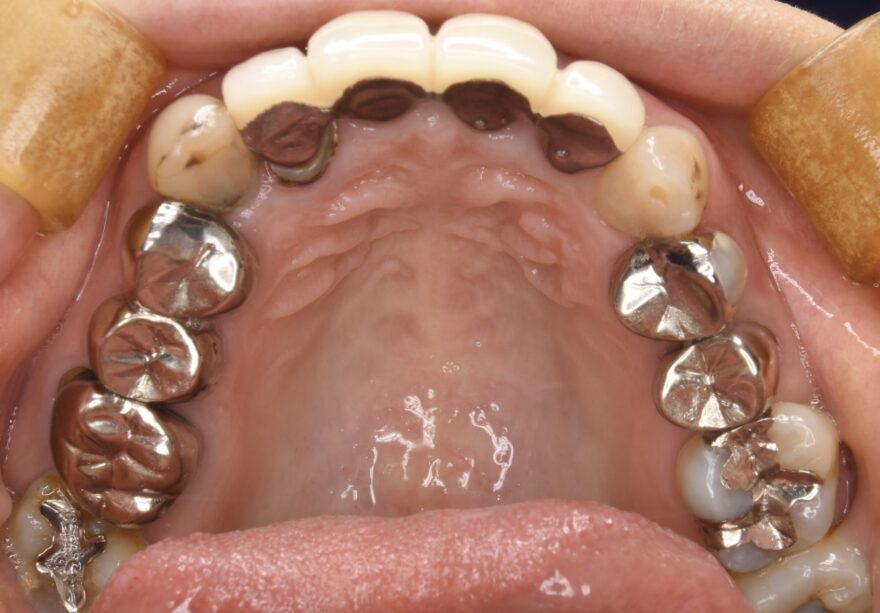

初診時の口腔内写真

銀歯の中が虫歯になっていることがわかります。

こちら側の銀歯も適合の問題を抱えていることがわかります。